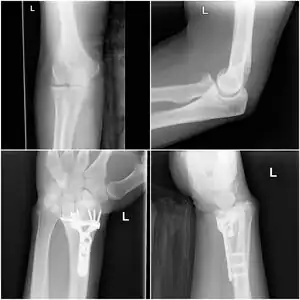

| Collated key points (combination of radial head fracture with dislocation of the distal radial ulnar joint, requiring pinning) | |

The Essex-Lopresti fracture is a break in the forearm near the wrist with concomitant dislocation of the distal radio-ulnar joint and disruption of the interosseous membrane.[1]

The injury can be difficult to diagnose initially as the attention is focused on the injury to the radial head, leading to the distal radio-ulnar injury being overlooked. The examination finding of tenderness of the distal radio-ulnar joint suggests an Essex-Lopresti injury in people who have sustained high energy forearm trauma. Plain radiography shows the radial head fracture, with dorsal subluxation of the ulna often seen on lateral view of the pronated wrist.[1]

The radial head fracture is usually managed by open reduction internal fixation; if the fracture is too comminuted, a radial head implant can be used. Excision of the radial head should be avoided, as the radius will migrate proximally leading to wrist pain and loss of pronation and supination of the wrist. Delayed treatment of the radial head fracture will also lead to proximal migration of the radius.[4]

The distal radio-ulnar joint dislocation can be reduced by supination of the forearm, and may be pinned in place for 6 weeks to allow healing of the interosseous membrane.[1]